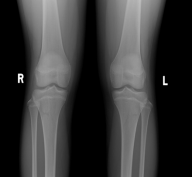

骨骺线是骨骺与干骺端之间的软骨,又称为“骺板”或“生长板”,在儿童腕掌指骨及膝关节的X光片上表现为一条较宽的透光带,它的闭合程度直接关系到孩子还有多少长高空间。

1.骨骺线未闭合:软骨还能继续骨化,孩子仍有很大长高潜力,这是正常生长的“黄金期”。

2.骨骺线部分闭合:软骨逐渐减少,生长速度放缓,剩余长高空间有限(通常每年增长不超过2-3cm)。

3.骨骺线完全闭合:骨骼停止生长,身高基本定型(仅脊柱可能有1-2cm弹性增长)。